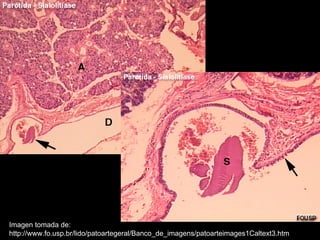

La sialolitiasis es la formación de obstrucciones mineralizadas en las glándulas salivales, causadas por el depósito de calcio y fósforo. Puede presentarse en las glándulas salivales mayores y menores, causando inflamación e hinchazón e incluso dolor durante las comidas. Los sialolitos se ven en radiografías como densidades radiopacas de varias formas y tamaños dentro de los conductos glandulares. El diagnóstico diferencial incluye otras imágenes radiopacas en los tejidos blandos.